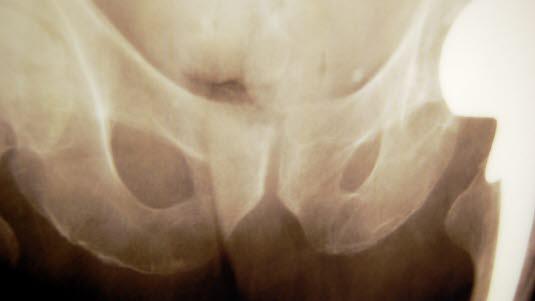

Tegn til bekkenskade kan være smerte, hevelse og at den skadede er ute av stand til å gå. Illustrasjonsfoto: Colourbox

Bekkenskade

Førstehjelp, symptomer og tegn ved bekkenskade.